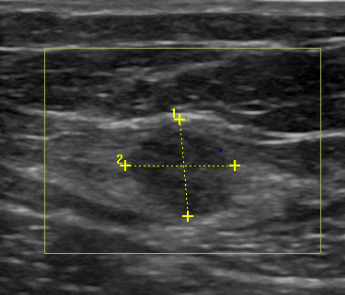

We present the case of a 28-year-old woman with a personal history of cesarean delivery 7 years ago who consulted due to pain relating to a mass in her right lateral abdominal wall. Physical examination showed a 2 cm nodular mass at the right lower quadrant, 10 cm away from the Pfannenstiel scar. Palpation was painful and no protrusion was felt after Valsalva or during bipedestation. Ultrasound and CT scan showed a 17 mm nodular mass at the union of oblique muscles and rectus abdominis muscle. With these findings we performed surgery to remove the mass and the specimen analysis confirmed endometrioma.